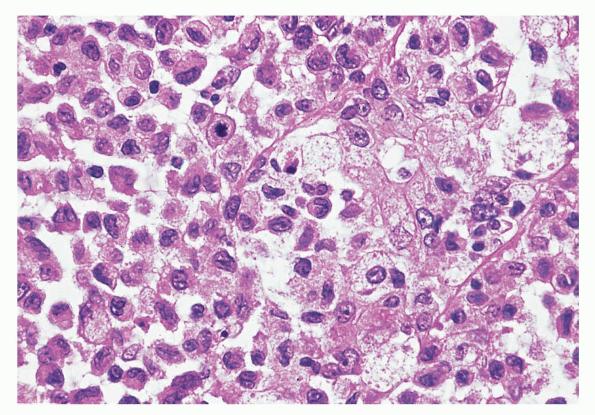

Langerhans cell histiocytosis = كثرة الخلايا الناسجة لانغرهانس

OLYMPUS DIGITAL CAMERA